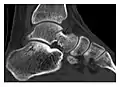

The greater tuberosity of the humerus is also an illustrative location of occult fractures. The osseous injury may follow seizures, glenohumeral dislocation, forced abduction, or direct impaction. They are commonly discovered on MRI in symptomatic patients with suspicion of rotator cuff tear. Coronal images are best suited for detection. They appear as crescentic oblique lines surrounded by a bone marrow edema pattern (Figure 5). The rotator cuff must be inspected since associated ligamentous lesions are common. In the ankle, malleoli and tarsal bones should be checked carefully for any cortical disruptions and radiolucent lines that may reveal a fracture. Awareness of the exact location of the pain will help direct the attention of the interpreter when searching for very subtle signs of fracture (Figure 6).[1]

Figure 6: Subtle anterior talar fracture in a 39-year-old man presenting with ankle pain after a fall. (a) Anteroposterior radiograph shows a subtle oblique radiolucent line through the talus (white arrows). (b) Sagittal CT reformation confirms the presence of an anterior talar fracture with cortical offset (black arrow). Avulsion fractures, which consist of a detached bone fragment resulting from a ligament or tendon pulling away from the bone, may also present with subtle radiographic signs. Tiny osseous fragments near the presumed attachment site of a ligament suggest this diagnosis. Common sites are the lateral tibial plateau (the Segond fracture), the spinal tuberosity of the tibia resulting from anterior cruciate ligament avulsion, and the ischial tuberosity.[1]